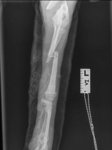

Wir treffen in Trikala, einer mittelgroßen Gemeinde auf dem griechischen Festland, ein. Vassiliki, eine 26-jährige Tierschützerin, die das Projekt an diesem Ort leitet und mich in den nächsten Tagen noch schwer beeindrucken wird, bringt uns direkt zu einer Tierarztpraxis, um Marla röntgen zu lassen. Außer den Vordergliedmaßen ist nichts gebrochen und auch die inneren Organe scheinen nicht verletzt zu sein. Dann bleibt „nur“ noch die Großbaustelle: ihre beiden vorderen Beinchen. Sie sind insgesamt an vier Stellen gebrochen. Welch himmelschreiende Ungerechtigkeit! Rechtzeitig vor einem elendigen Sterben am Straßenrand gerettet worden zu sein und dann vor nahezu unlösbaren Problemen zu stehen? Ich selber habe hier weder die Möglichkeiten, noch das Equipment, um Brüche zu operieren. Aber kapitulieren werden wir nicht. Keiner von uns. Auch Marla nicht, das haben wir uns beide ganz leise aber ganz fest versprochen.

Wenige Tage später ist Marla operiert. Mehrere Operationen waren erforderlich, um die komplizierten Brüche zu versorgen. Chirurgische Höchstleistungen machten es möglich, ihre Beine zu erhalten.